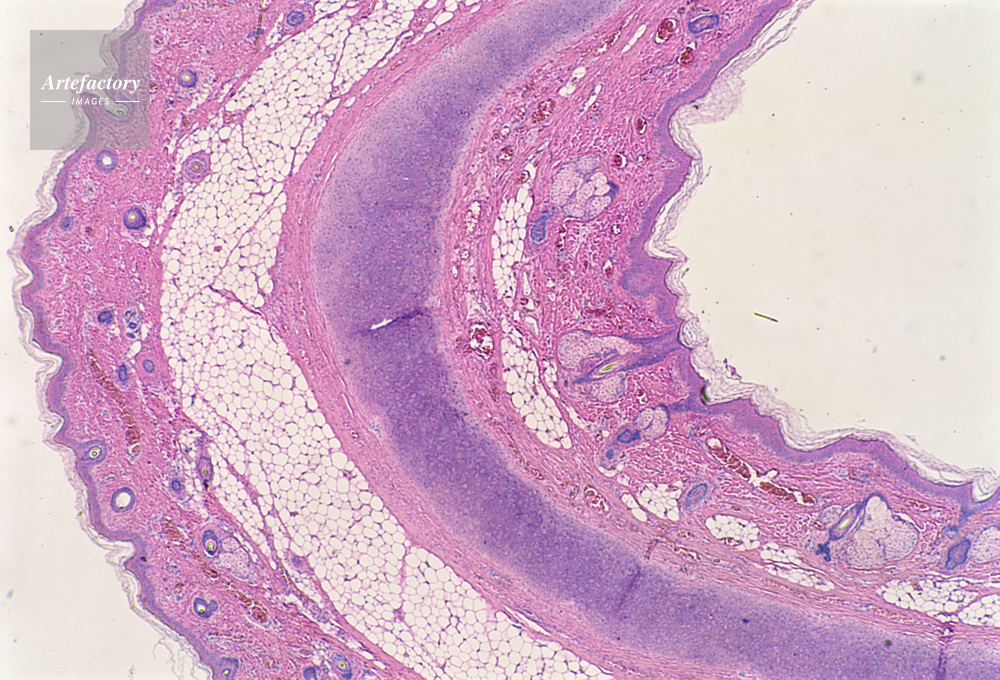

| キャプション | 胎児,外耳,人間,20倍, | 制限事項 | ||

| ソース | ピクセル数 | 5555px × 3775px | ||

| 撮影地 | 印刷サイズ | 30.3cm × 20.6cm | ||